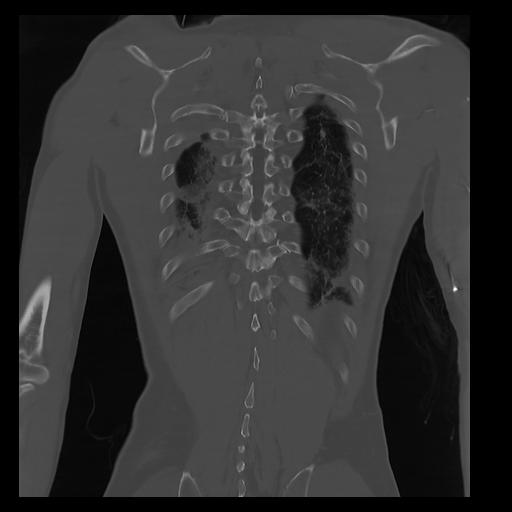

32 PULMON,CE,Coronal,3.000,PULMON,Coronal,